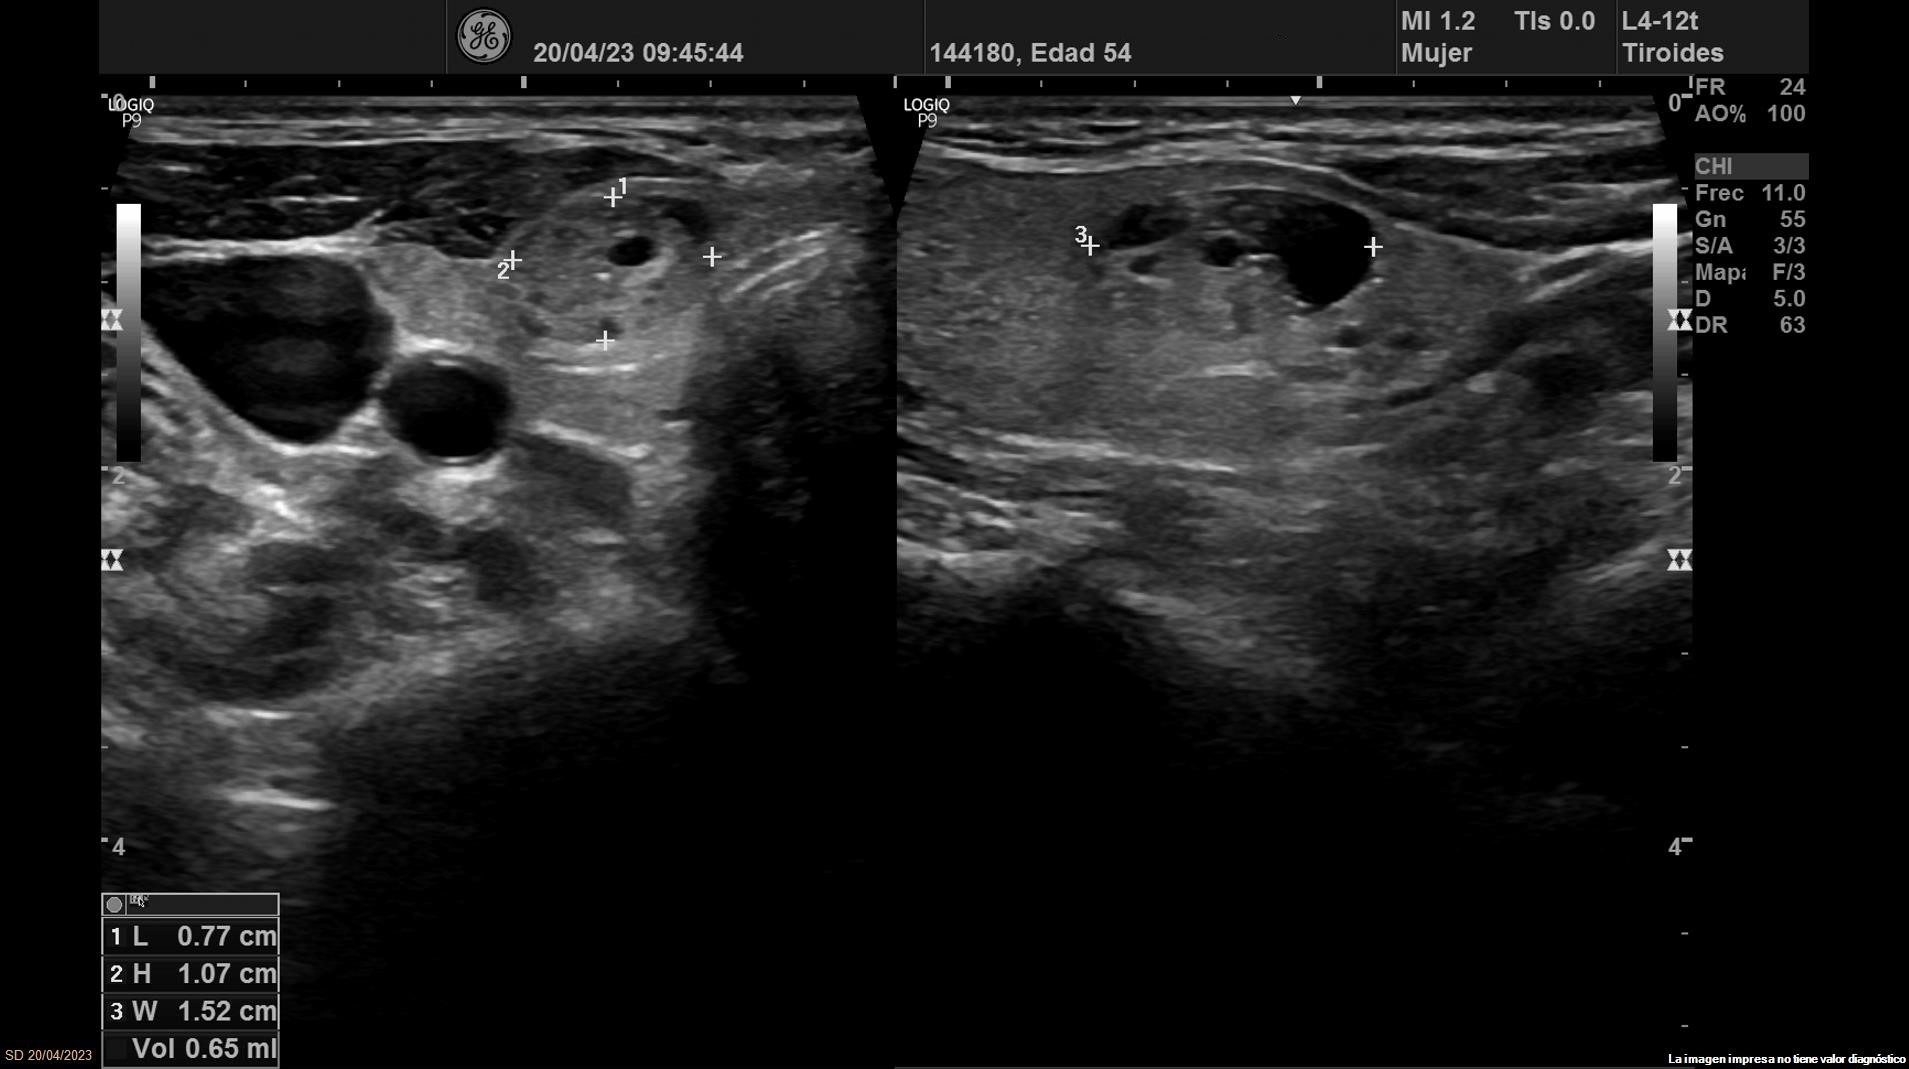

Se objetiva una adenopatía de 0,8 cm de aspecto benigno, ovalada y con bordes definidos. Además, se realiza ecografía tiroidea:

Ante los hallazgos obtenidos, nos planteamos el diagnostico diferencial entre los nódulos tiroideos benignos y malignos. Se deriva a Endocrinología donde realizan nueva ecografía que concuerda con la nuestra.

Se solicita biopsia PAAF obteniendo el diagnóstico definitivo de bocio nodular normofuncionante con estudio citológico de nódulo dominante izquierdo compatible con neoplasia folicular (Bethesda 4).